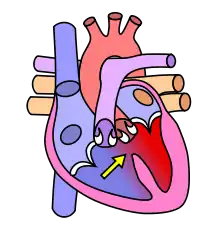

The cardiovascular system, in addition to needing to maintain itself within certain levels, plays a role in maintenance of other body systems by transporting hormones (heart secretes Atrial Natriuretic Peptide and Brain Natriuretic Peptide, or ANP and BNP, respectively) and nutrients (oxygen, EPO to bones,etc.), taking away waste products, and providing all living body cells with a fresh supply of oxygen and removing carbon dioxide. Homeostasis is disturbed if the cardiovascular or lymphatic systems are not functioning correctly. Our skin, bones, muscles, lungs, digestive tract, and nervous, endocrine, lymphatic, urinary and reproductive systems use the cardiovascular system as its "road" or "highway" as far as distribution of things such as nutrients, oxygen, waste products, hormones, drugs, etc. There are many risk factors for an unhealthy cardiovascular system. Some diseases associated are typically labeled "uncontrollable" or "controllable." The main uncontrollable risk factors are age, gender, and a family history of heart disease, especially at an early age.

The cardiovascular system also contains sensors to monitor blood pressure, called baroreceptors, that work by detecting how stretched a blood vessel is. This information is relayed to the Medulla Oblongata in the brain where action is taken to raise or lower blood pressure via the autonomic nervous system.